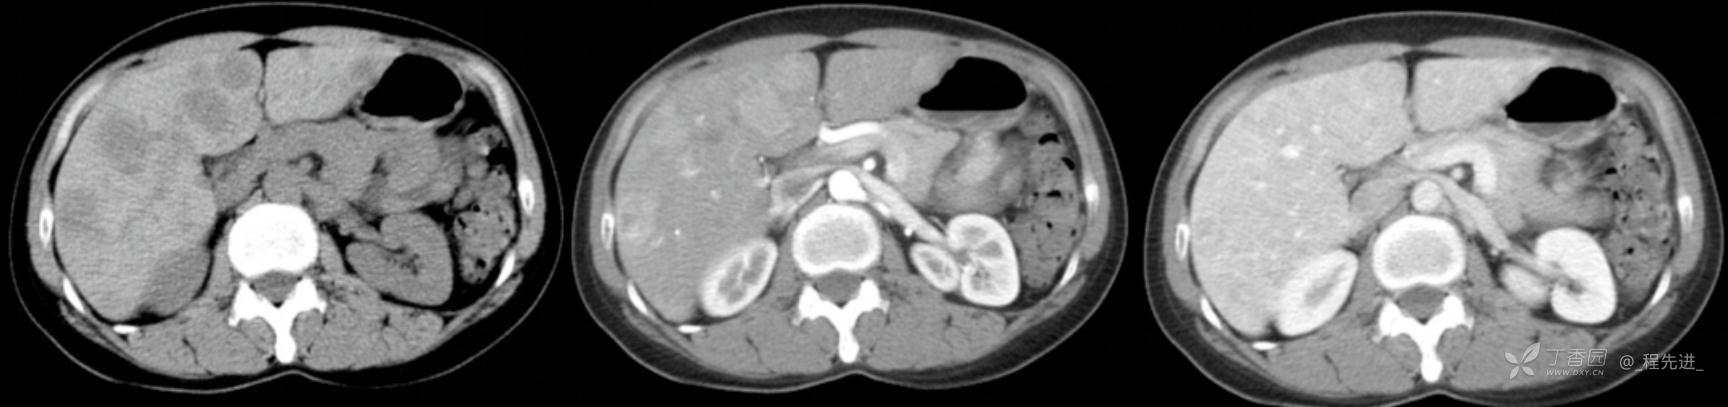

图像左边为平扫,中间的是动脉期,右边的是静脉期